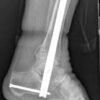

Hindfoot Nails And Geriatric Ankle Fractures

Ankle fractures can potentially limit an individual’s mobility, autonomy, and quality of life, making them devastating injuries for geriatric patients. Researchers from the Donald and Barbara Zucker School of Medicine at Hofstra/Northwell, in Hempstead, NY, wanted to better understand the functional outcomes and...